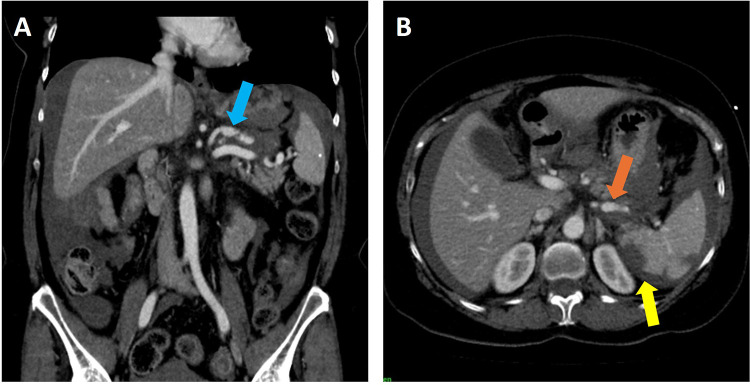

Alpha 1 Antitrypsin Deficiency (AATD) is a genetic condition that results from mutations in the SERPINA1 gene, which can lead to deficient or dysfunctional Alpha 1 Antitrypsin (AAT) protein production. AATD is linked to chronic obstructive pulmonary disease (COPD) and emphysema. In addition to pulmonary manifestations, AATD has also been associated with vascular pathology due to excessive protease activity, tissue degradation, and vessel stiffening. Early AATD diagnosis is crucial to prevent progressive lung damage and associated pathologies. Here, we present case reports of two patients with AATD from the Temple University Hospital Outpatient Clinic, who exhibited aneurysms of the aorta and splenic artery. AATD should be considered a genetic risk factor for aneurysms and vascular diseases, necessitating cardiovascular monitoring in affected individuals. This report emphasizes both the need for heightened awareness of AATD as a potential etiology of unexplained vascular aneurysms, as well as the need for screening for vascular pathology in patients with AATD-associated COPD and emphysema to facilitate early intervention and improve patient outcomes.

Abstract Image